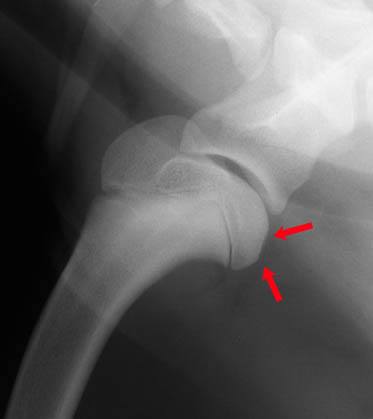

Cette carte de concepts créée avec IHMC CmapTools traite de: Ostéochondrite-dissécante-Roxanne, ∘ Examen externe : où l'on recherche Une limitation des amplitudes d'extension et de flexion, due à la douleur, ∘ Traitement chirurgical : Curetage de la lésion, Les chiens en croissance entre 4 et 10 mois, en particulier les mâles. Tels que Rottweiler, ∘ Examen externe : où l'on recherche Une boiterie qui s'aggrave à l'effort, Les chiens en croissance entre 4 et 10 mois, en particulier les mâles. Tels que Golden retriever, ∘ Examens complémentaires : Ponction articulaire → Afin d'exclure l'arthrite, ∘ Examen externe : où l'on recherche Un épanchements et des crépitements articulaires, Les chiens en croissance entre 4 et 10 mois, en particulier les mâles. Tels que Berger allemand, Les chiens en croissance entre 4 et 10 mois, en particulier les mâles. Tels que Labrador, Ostéochondrite dissécante entraîne Ostéite + Synovite, Les chiens en croissance entre 4 et 10 mois, en particulier les mâles. Tels que Setter, ∘ Traitement chirurgical : Extraction des fragments cartilagineux, ∘ Examens complémentaires : Radiographie → Afin d'exclure la fracture → Recherche de lésions d'OCD